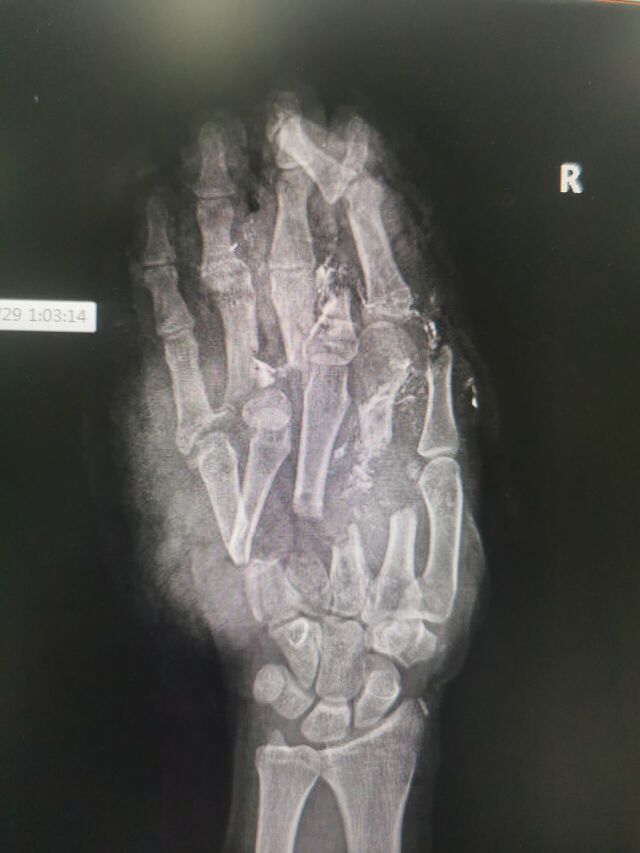

注定又是一个不眠夜!

16岁手进绞肉机了

IMG_20250923_101745.jpg

IMG_20250929_150141.jpg

IMG_20250929_150124.jpg